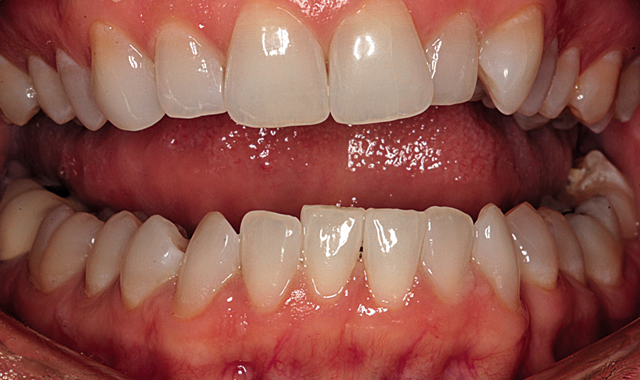

Mary’s smile as she presented is shown in Figure 1. In the retracted view (Fig. 2) the malalignment is obvious. She was not concerned about the tipped maxillary premolars, but rather wanted to focus on the six anterior teeth.

Fig. 1

Fig. 2